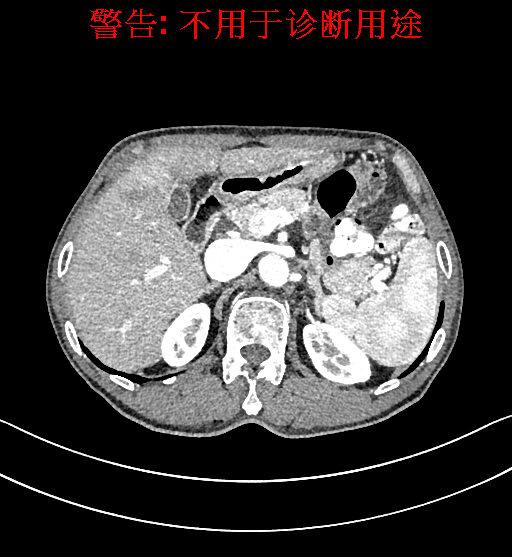

术前CT检查:

动脉期

上腹部动态CT扫描示肝左内叶占位,考虑肝Ca可能性大,请结合临床肝多发小囊肿。

通过调节窗宽窗位调整CT序号,对肿瘤,肝实质,胆囊,下腔静脉,肿瘤,肝动脉、门静脉及肝静脉等进行三维重建;系统自动计算肿瘤体积和肝脏体积。模拟手术操作,自动计算切除肿瘤体积。肝脏体积为1320ml,肿瘤体积为37.88ml,通过比对70-80岁正常肝脏体积为1263.13±170.25 ml,通过术前模拟手术,精准判断切除后剩余肝脏体积能耐受,避免肝衰竭发生。